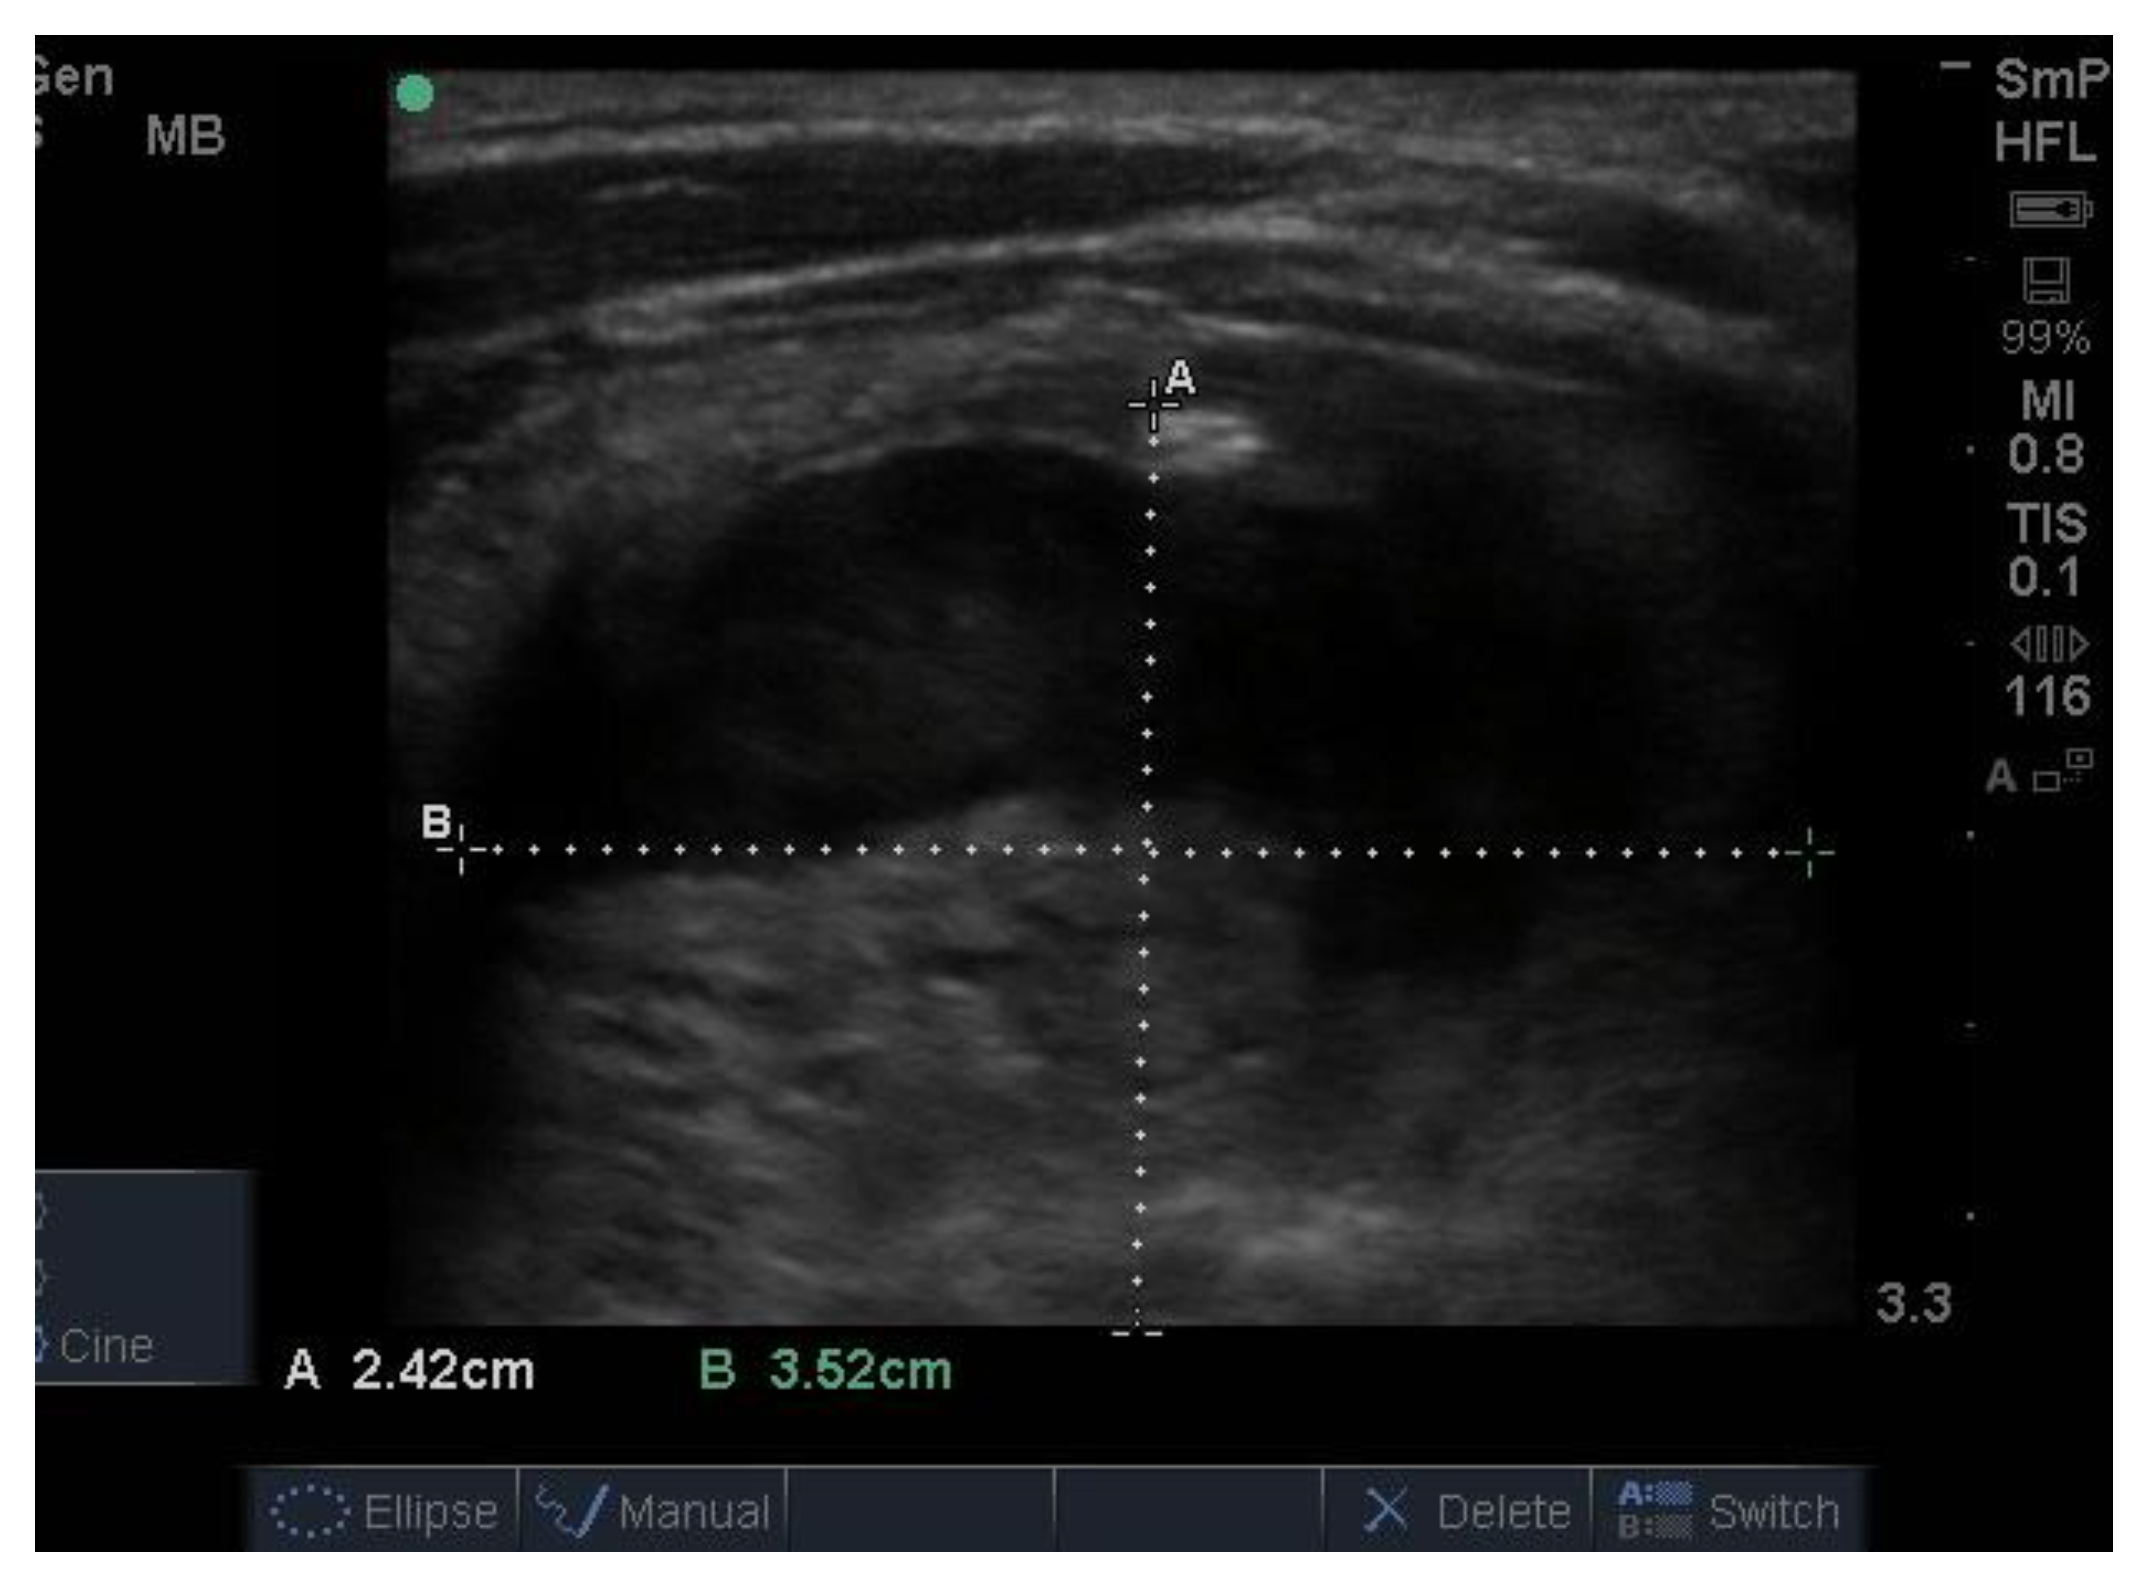

Follicular nodules are much less common than colloid nodules with a different appearance on ultrasound; they are more cellular, giving a solid appearance, with a whitish colour, i.e., less hypoechoic. They too have a sharp edge and halo and grow slowly over time [5]. The problem with these lesions is that FNAB is unable to differentiate between a benign follicular adenoma and follicular cancer, and if the latter is suspected, thyroid surgery is the final arbitrator. About 10% of benign thyroid nodules are follicular, and most of them end up being removed. Two examples of follicular nodules that were finally proven to be benign are shown in Figure 4. On follow-up ultrasound (US), 6–12 months later, repeat biopsy might be indicated if a nodule has grown by 20% or more in two or more dimensions; benign nodules also grow, but less quickly.

Figure 4.

Two examples of follicular nodules that were shown at surgery to be benign. The nodules are roughly oval shaped, slightly hyper echoic and have sharp edges and, particularly, the bigger of the two, thick halos.